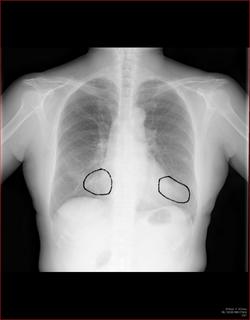

3Dだと、こうなります。

気管狭窄ですね。こういう所見もレントゲンで捉えることができるのです。